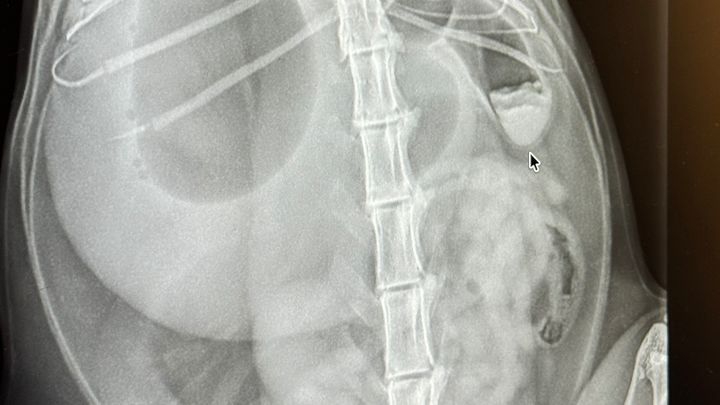

Our beloved Pinto has to get surgery due to a foreign object that is blocking his intestines and hasn’t ate since Wednesday 04/01/26. He’s been in pain and surgery is the only way. I never ask anyone for help with the kitties, but everyone who meets him can tell you that he’s the sweetest boy ever and doesn’t deserve to be in pain. Since Bryan is deployed, it’s just me taking care of the kitties and funds are low asa I am full time student. If you can donate to his surgery fund that will be amazing and very appreciated. Thank you